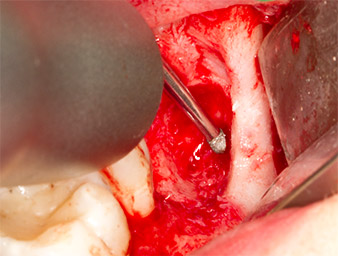

Periapical inflamed tissue was also removed very carefully with a manual excavator. Fig. 12 shows the empty alveole with exposed inferior alveolar nerve.

inferior alveolar nerve

Fig. 12: The inferior alveolar nerve can be seen in the bottom of the alveole.

Subsequently, the autogenous bone tissue (Fig. 13) was placed into the alveole and the surrounding bone defect (Fig. 14). Collagen fleece covered the bone chips up to bone level as protection for the exposed nerve (Fig. 15). Sutures using vicryl thread, USP 4.0, were used to close the opened up soft tissue (Fig. 16). An Ibuprofen preparation (Seractil 400 mg, 3x1) and an antibiotic consisting of amoxicillin and clavulanic acid (Augmentin 1 g, 2x1) were prescribed postoperatively.